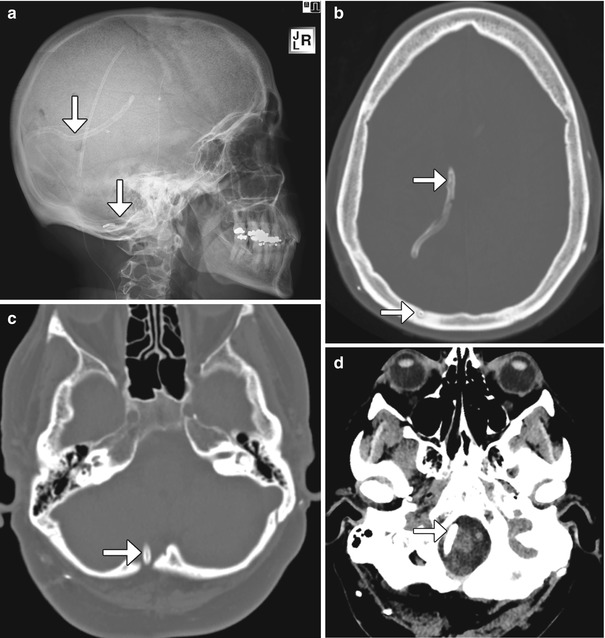

From radiologykey.com

Imaging of Cerebrospinal Fluid Shunts, Drains, and Diversion Techniques Are Non Programmable Shunts Mri Safe Hydrocephalus is the accumulation of cerebrospinal fluid in the brain, resulting from. If the shunt is known not to be a programmable shunt, then 1.5t and 3t mri may safely proceed. Brief summary of known devices. If it is established that a shunt is a. Mri safety policy for patients with csf shunts e.g. Cerebrospinal fluid (csf) shunt valves and. Are Non Programmable Shunts Mri Safe.

Imaging of Cerebrospinal Fluid Shunts, Drains, and Diversion Techniques Are Non Programmable Shunts Mri Safe If the shunt is known not to be a programmable shunt, then 1.5t and 3t mri may safely proceed. Mri safety policy for patients with csf shunts e.g. If it is established that a shunt is a. Hydrocephalus is the accumulation of cerebrospinal fluid in the brain, resulting from. Cerebrospinal fluid (csf) shunt valves and accessories. Brief summary of known. Are Non Programmable Shunts Mri Safe.